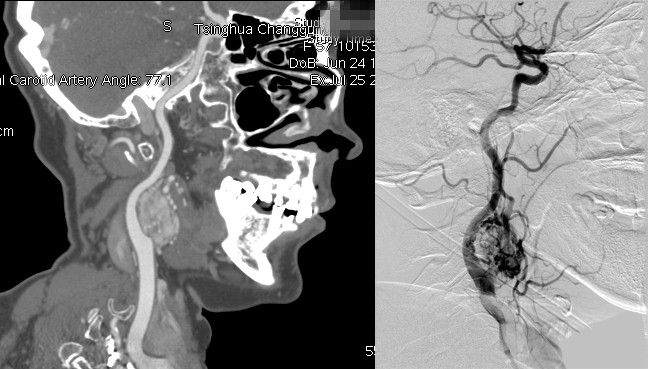

图1 患者于门诊行CTA检查(左:重建像,右:断面像),右侧颈部肿物位于颈动脉分叉处,长径约5cm,包绕颈内动脉与颈外动脉(Shamblin 3型)。